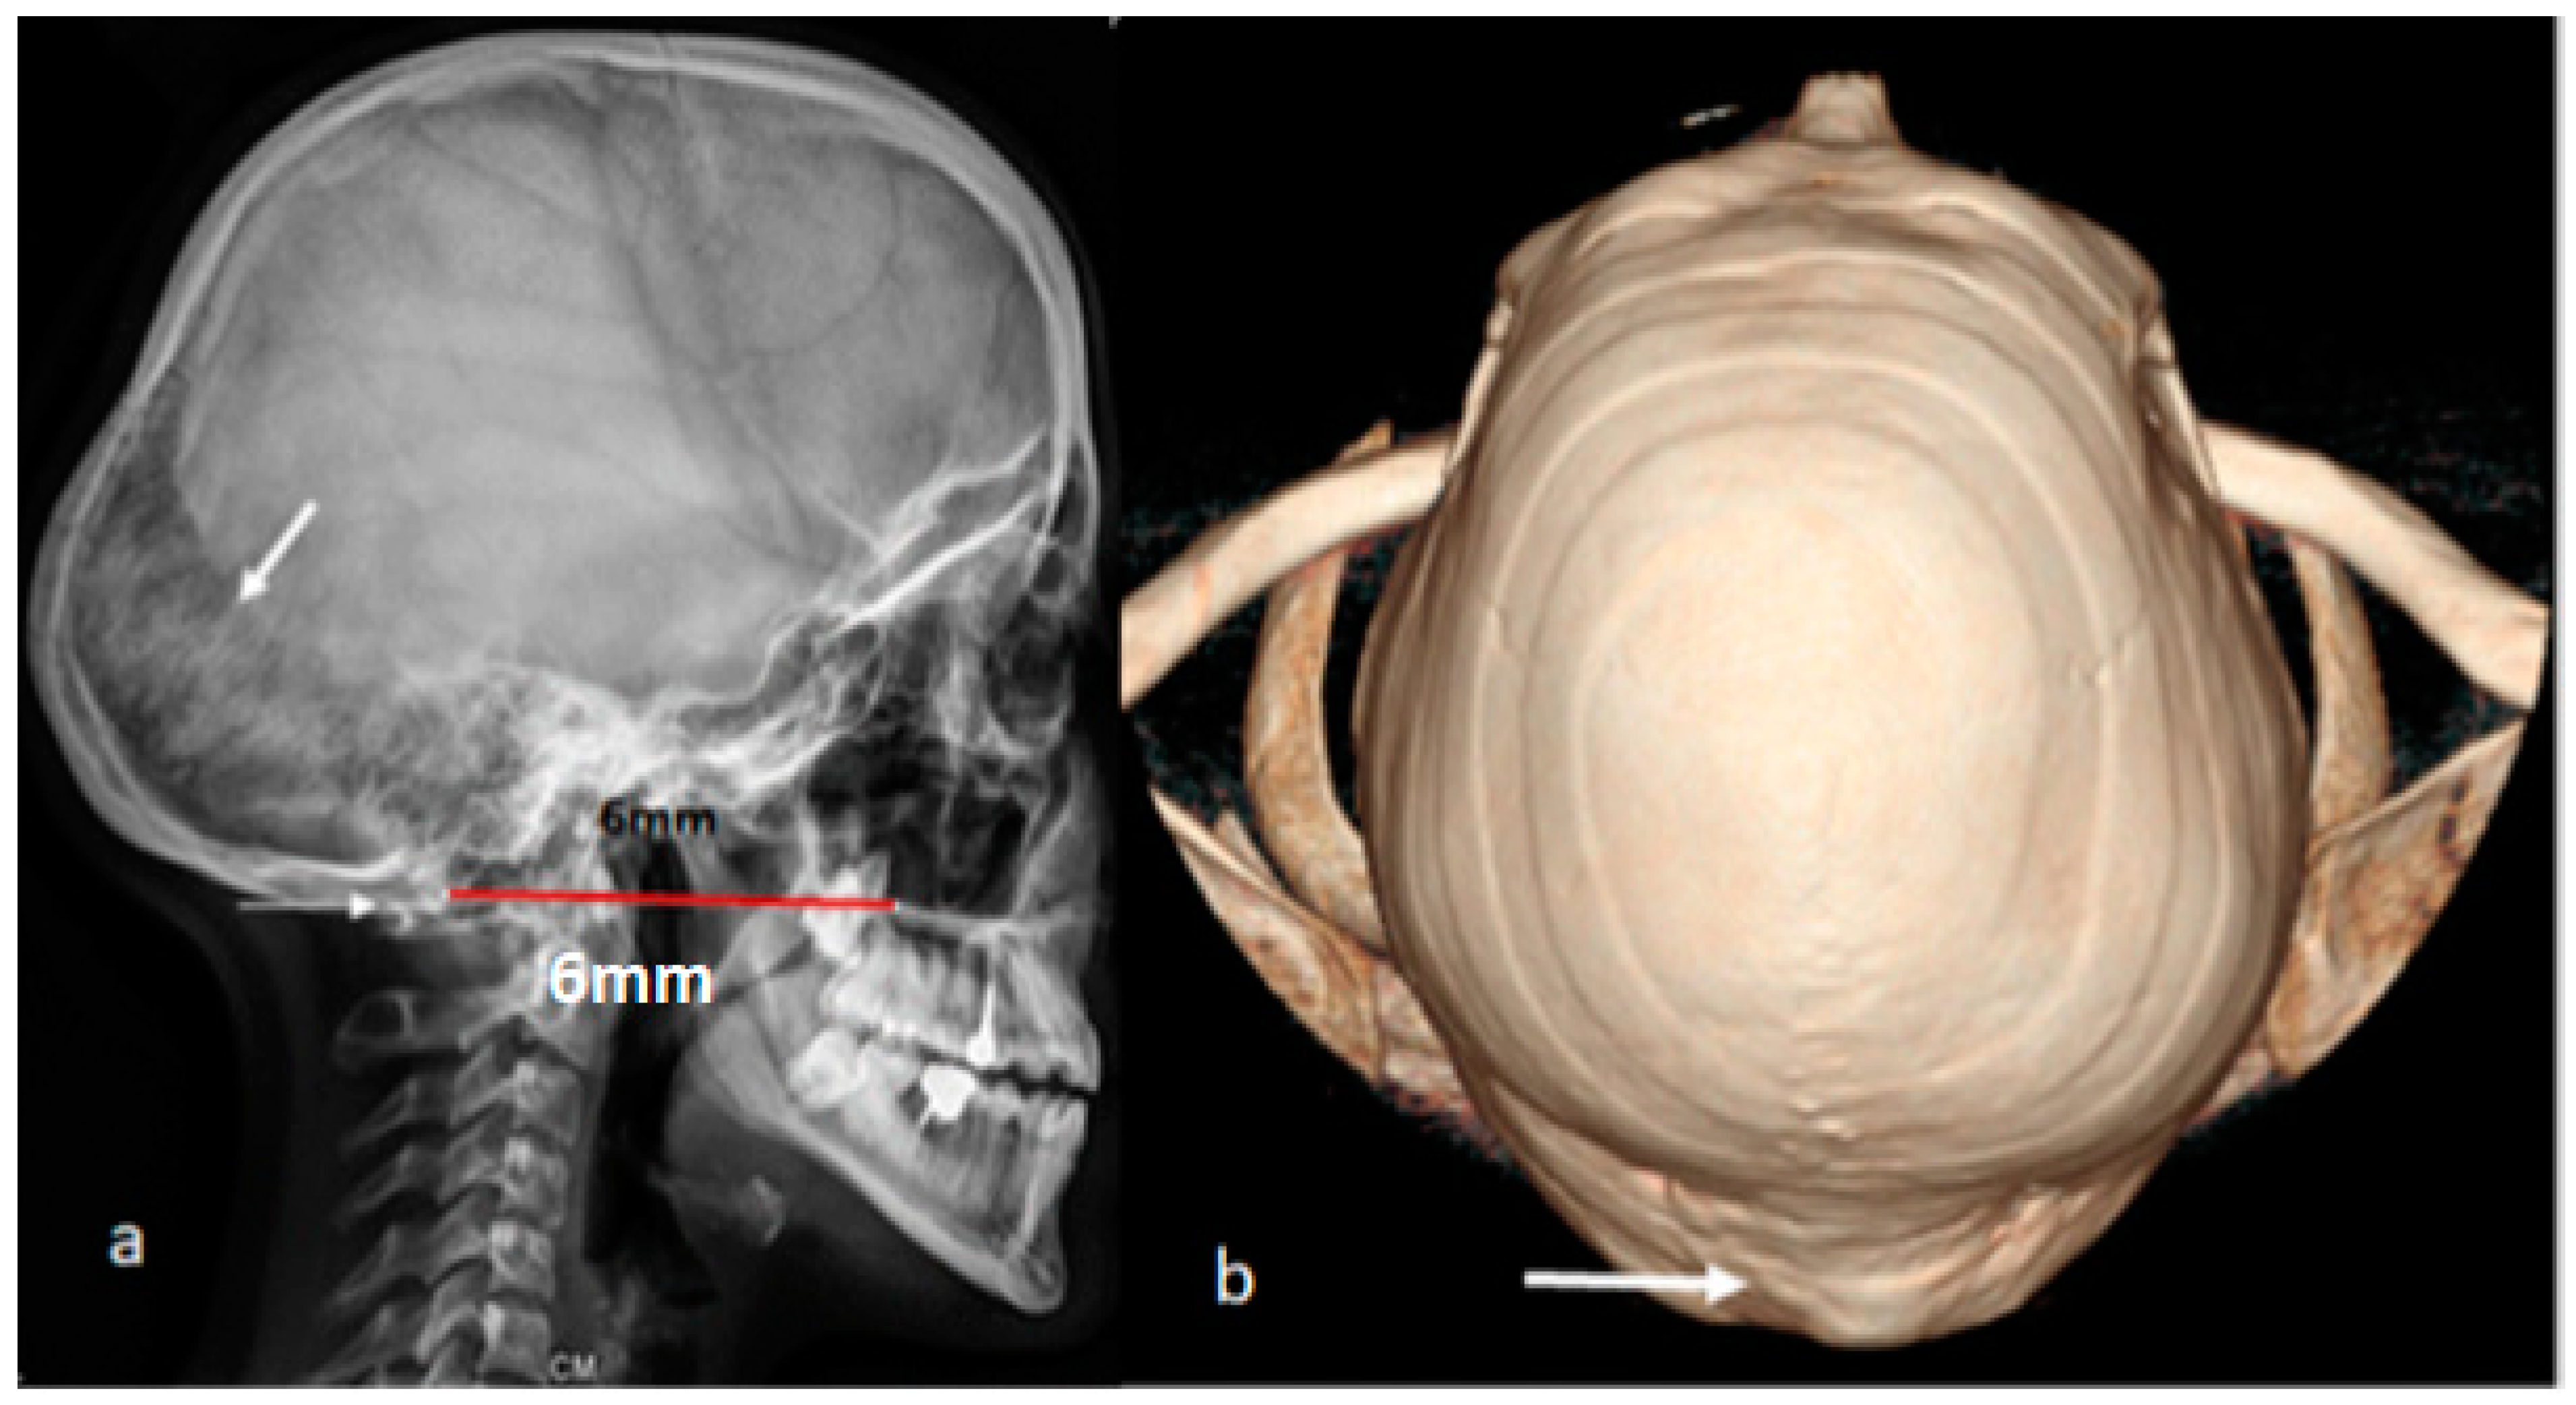

3.1. Patients with Osteogenesis Imperfecta Type I

Patients with Osteogenesis Imperfecta Type IVB